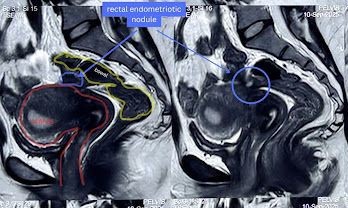

Case 2: A 33-year-old unmarried woman presented with severe dysmenorrhea, right iliac fossa pain, and constipation. Preoperative MRI suggested deep infiltrating endometriosis with probable rectal muscularis involvement (Figure 1). Following saline hydrodissection, intraoperative Endo-USG demonstrated superficial mucosal involvement without muscularis infiltration (Figure 2). Based on these real-time findings, conservative rectal shaving was performed instead of the initially planned disc excision (Figure 3,4). Histopathology confirmed superficial endometriosis. At six-month follow-up, the patient reported marked improvement in dyschezia and constipation. Summary of the two cases in table 1 and comparison with the study data with data in literature in table 2.

Figure 1: Both sides rectal endometriotic nodule on MRI